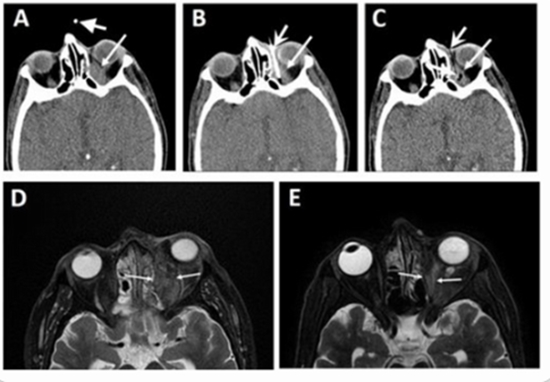

Purpose : A high incidence of sinu-orbital Mucormycosis as a fulminant and opportunistic fungal infection happened following the COVID-19 pandemic. Traditionally, patients with apical or extensive orbital involvement are candidates for exenteration. We designed and applied CT scan guided orbital amphotericin C delivery. In this study we aimed to report this novel technique and results of this method in control of orbital mucormycosis with apical involvement.

Results : A total of thirty patients with mean age of 52±11.86 were enrolled in this study. Twenty-three (76.7%) patients were male; group A: 11 (73.3%) and B: 12 (80%). The majority of the patients in both group were diabetics (A: 10 (66.7%), B: 10 (76.9%)). Most patients in both groups had received corticosteroids and antiviral therapy for their recent COVID-19, 23 (82.1%) and 25 (89.3%), respectively. No patient in group A underwent exenteration. Eleven (78.6%) patients in group B underwent orbital exenteration. Of the 6 expired patients, 5 (83.3%) were in group B (P<0.0001). Peri-orbital ecchymosis and intracranial air extension were observed in 2 (13.3%) and 1 (6.7%) in group A patients, respectively.

Conclusions : Intra-orbital amphotericin injection under CT-guidance can be considered as a highly effective method in patients with orbital mucormycosis. This method may decrease exenteration without increasing mortality of patients.